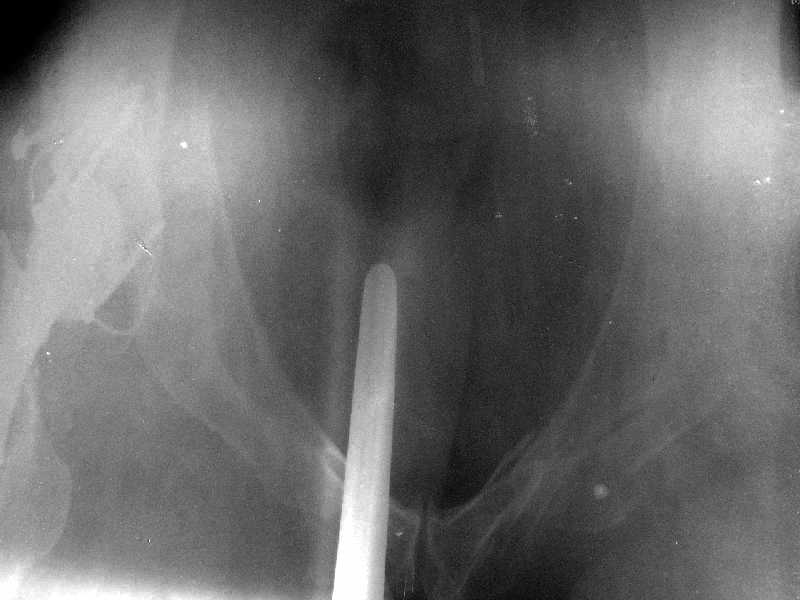

Получила поперечный перелом правой вертлужной впадины (снимок прилагается) с переломом ветвей лонной кости на другой стороне (inletview также в приложении), а также поперечный перелом дистального метафиза бедра на этой же стороне. Что посоветуете в отношении протеза и впадины? Спасибо заранее.

A colleague of mine from another hospital requests opinion. A female 39 years old was operated ~1 year ago - right side THA for hypoplastic hip. Yesterday she was going to the hospital for THA ofthe second hip but got involved in a car accident.She admitted with right acetabular and left rami fractures (images attached). Also trasverse fracture of the right distal femur.Seeking your advice regarding the acetabular fracture. THX!